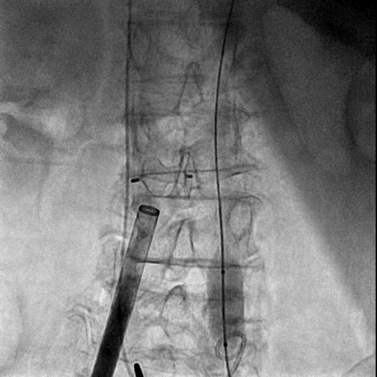

将0.014英寸导丝交换为超硬导丝后,置入22F大鞘达腹主动脉内。

经右侧股静脉沿超硬导丝置入22F大鞘达腹主动脉内

完成瓣膜置入后撤出22F输送鞘并用封堵器封堵腹主动脉与下腔静脉间的动静脉瘘,封堵器完全释放后腹主动脉及下腔静脉内造影均显示封堵效果良好,未见明显造影剂外渗。

封堵器释放后腹主动脉造影

封堵器释放后下腔静脉造影